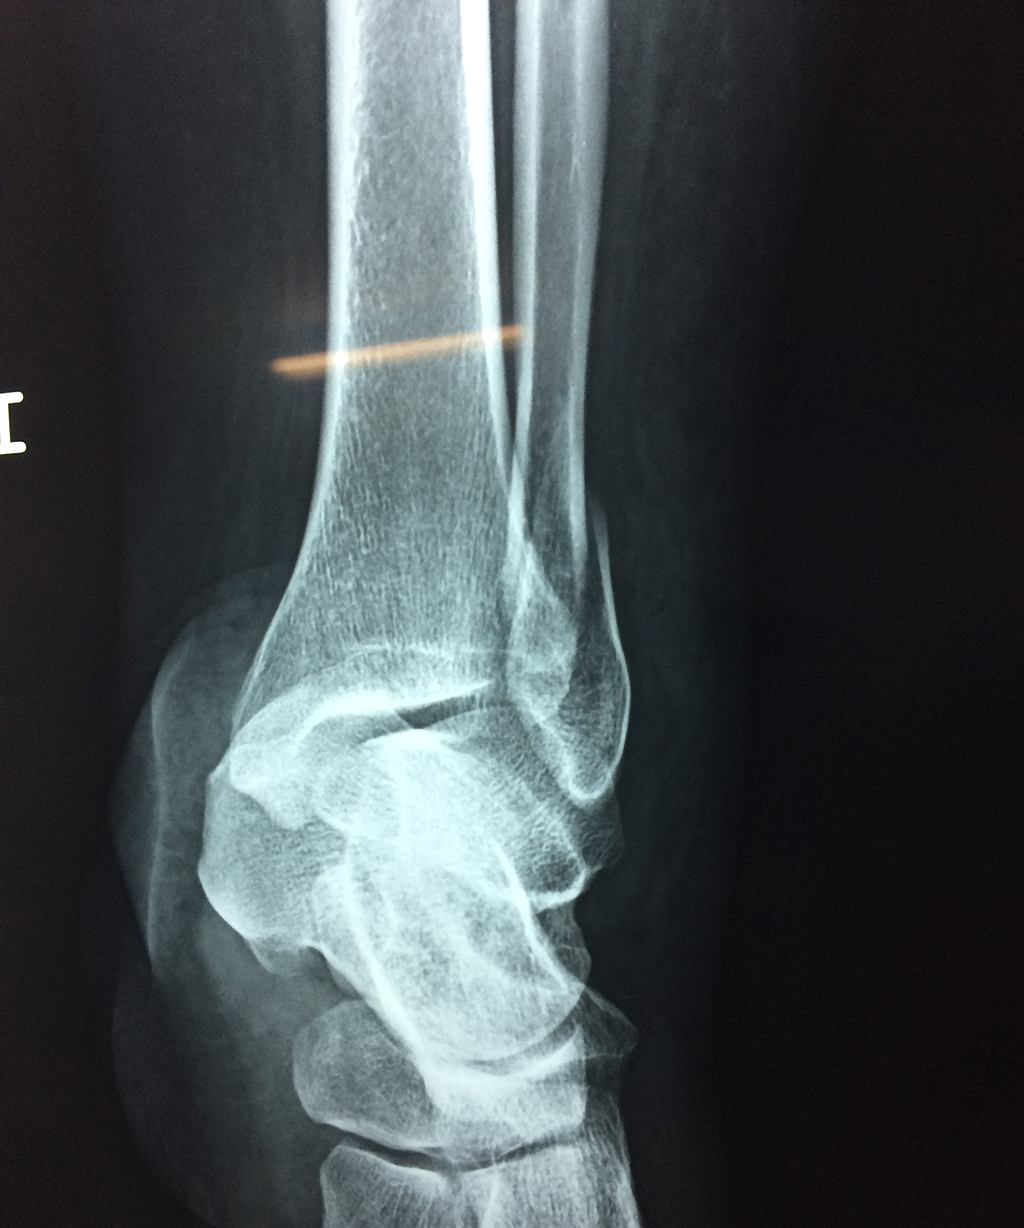

Una fractura de tobillo es la rotura de uno o más de los huesos del tobillo. Estas fracturas pueden ser:

- Parciales (el hueso está sólo parcialmente fisurado, no del todo).

- Completas (el hueso está perforado y está en 2 partes).

- Producirse en uno o ambos lados del tobillo.

Algunas fracturas de tobillo pueden requerir cirugía si:

- Los extremos de los huesos están desalineados entre sí (desplazados).

- La fractura se extiende hasta la articulación del tobillo (fractura intra-articular).

- Los tendones o ligamentos (tejidos que sujetan los músculos y los huesos entre sí) están rotos.

Cuando se necesita cirugía, es probable que esta implique el uso de clavijas de metal, tornillos o placas para sostener los huesos en su lugar mientras la fractura se consolida. Los elementos de soporte pueden ser temporales o permanentes.